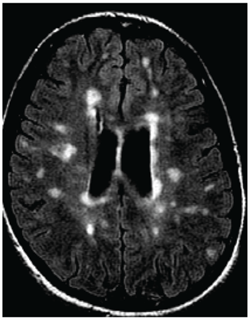

The study presented at SIR 2017 was also led by Traboulsee and included 104 patients. All patients had a catheter inserted into their blocked veins, but only 49 underwent venoplasty, in which their vessel walls were expanded by a small inflated balloon. The study was double-blinded: Neither patients nor the physicians treating them knew who received the actual procedure. The researchers used MRI to evaluate the results.